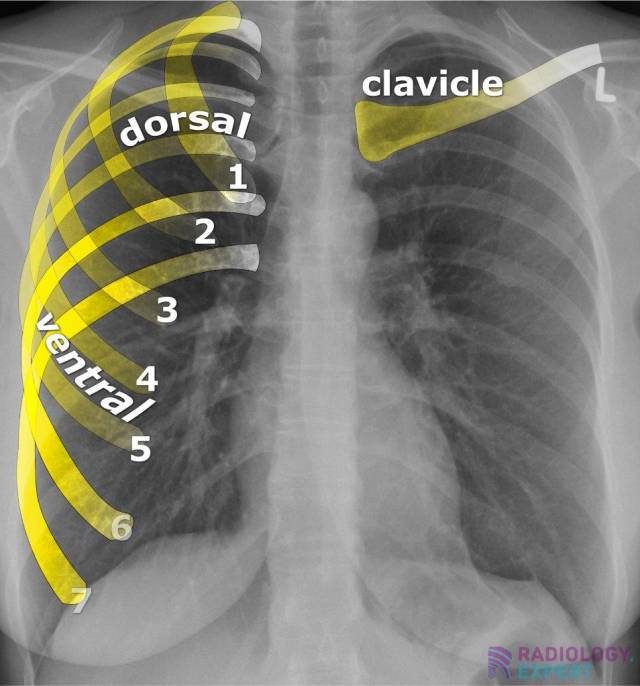

From www.radiology.expert

Chest Xray Chest X Ray Adequate Exposure Always assess inspiration and lung volumes. In fact every radiologst should be an expert in chest film reading. Cxr is a quick, noninvasive,. (cxr) is one of the most commonly performed imaging studies in clinical practice. Incomplete inspiration can lead to exaggeration of lung markings and heart size. The space between the medial. Loss of the hemidiaphragm contour or of.. Chest X Ray Adequate Exposure.